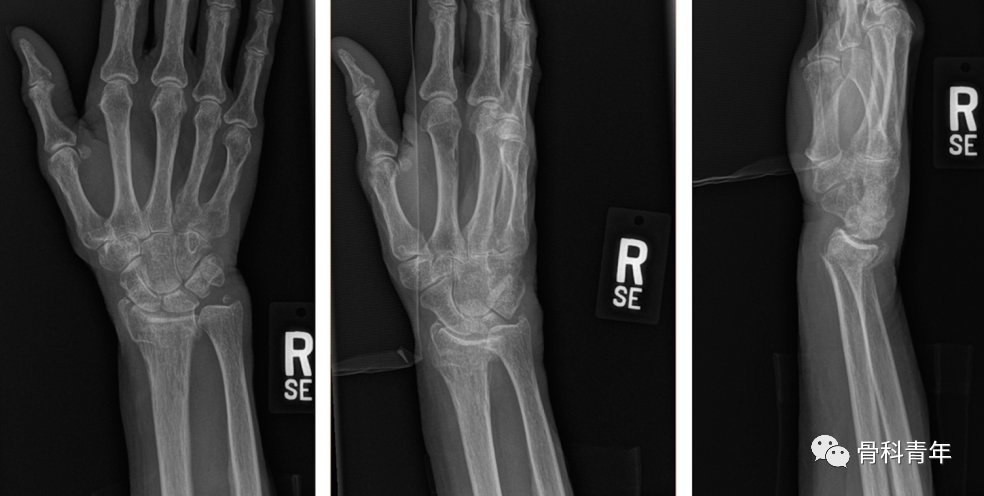

三、PEEK锁定钢板

PEEK钢板存在以下特性:

透视下不显影,利于术中观察骨折复位情况及评估骨折愈合情况;

与骨皮质弹性模量相近,避免应力遮挡效应;

PEEK材料与金属螺钉,避免冷焊接。